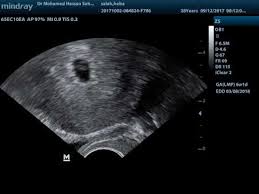

الأسبوع الخامس كيس الحمل شكل الجنين في الشهر الاول بالسونار

شكل الجنين في الشهر الاول بالسونار 3a2ilati

شكل الجنين في الشهر الاول بالسونار و سبب صغر كيس الحمل مجلة أبدعي